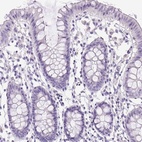

Immunohistochemistry analysis in human pancreas and colon tissues using Anti-PDIA2 antibody. Corresponding PDIA2 RNA-seq data are presented for the same tissues.